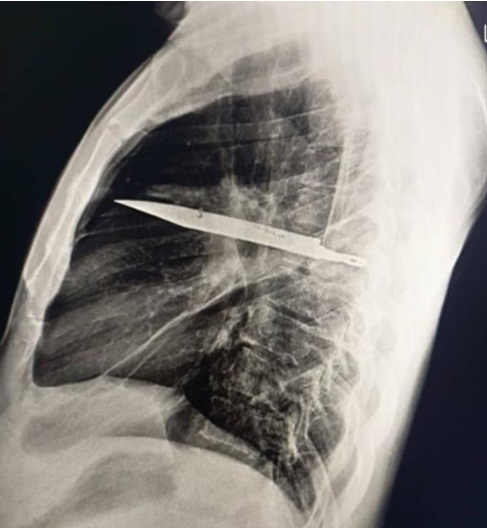

O raio-x atual revelou a presença da lâmina presa no lado direito do tórax, próxima à escápula. Apesar do risco, o objeto não atingiu órgãos vitais. Segundo os médicos, o acúmulo de pus se formou devido à presença do corpo estranho e à lesão nos tecidos ao redor.